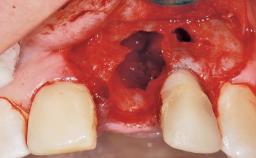

A 42-year-old female patient was referred to our clinic at the School of Dentistry of the University of São Paulo in November 2004, presenting a deficient restoration in the upper left central incisor. The clinical examination revealed no gingival retraction or any signs of gingival inflammation and, therefore, previous periodontal treatment was not considered. The patient presented a high lip line at full smile and a thin tissue biotype. This combination characterized a high-risk situation from an anatomic point of view, which required careful preoperative planning and cautious surgical execution.

Placement Protocol Immediate implant placement

Socket Morphology Single-root socket

Socket Integrity Sufficient, with intact bone walls